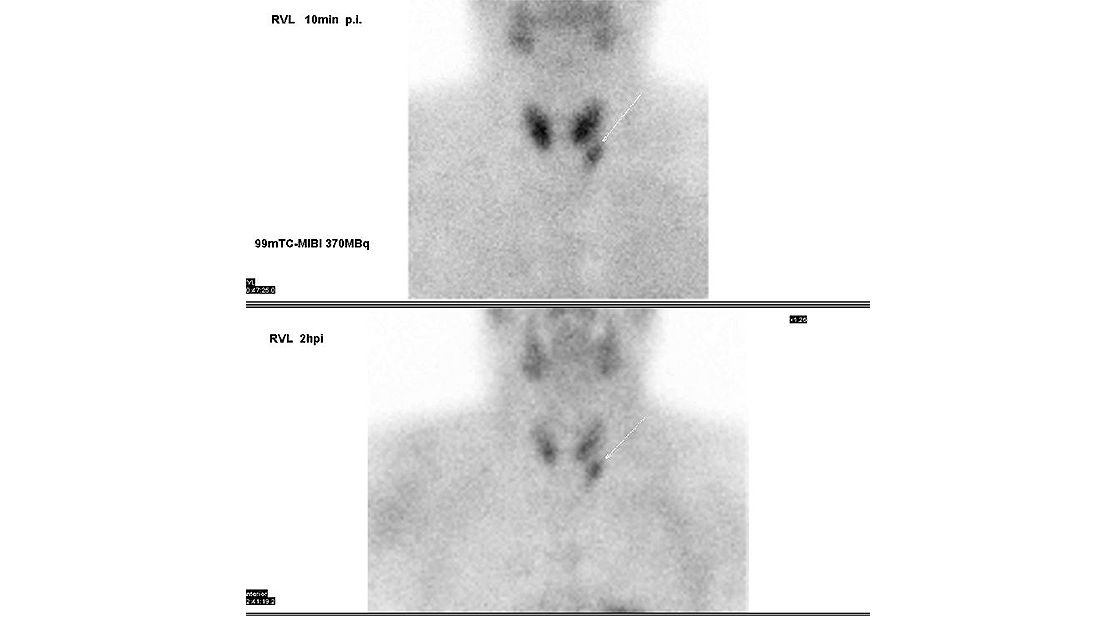

Wir untersuchen die Nebenschilddrüsen mit einer Szintigraphie, wenn bei einem Patienten geprüft werden soll, ob er an einer Überfunktion der Nebenschilddrüsen leidet, dem Hyperparathyreoidismus (HPT).

Dem Patienten wird hierfür eine schwach radioaktiv markierte Substanz gespritzt, die sich selbstständig den Weg aus dem Blut hin zu den Nebenschilddrüsen sucht und sich dort anreichert.

Zehn Minuten später kann die eigentliche Untersuchung beginnen. Dafür platzieren wir den Patienten auf der Untersuchungsliege liegend. Die Gamma-Kamera hält dann fest, wie sich das radioaktive Medikament in den Nebenschilddrüsen verhält. Dieses erste Szintigramm dauert 10 Minuten.

Nach 1 bis 1,5 Stunden Wartezeit, in denen der Patient die Räume der Nuklearmedizin auch verlassen kann für einen Spaziergang oder einen Kaffee, werden weitere Aufnahmen gemacht, wieder liegend.

Mit einer SPECT/CT-Untersuchung erhalten wir eine errechnete 3D-Darstellung. Zusätzlich machen wir ein weiteres Szintigramm. Insgesamt dauern die beiden Untersuchungen etwa 30 Minuten, in denen der Patient ruhig liegen sollte.